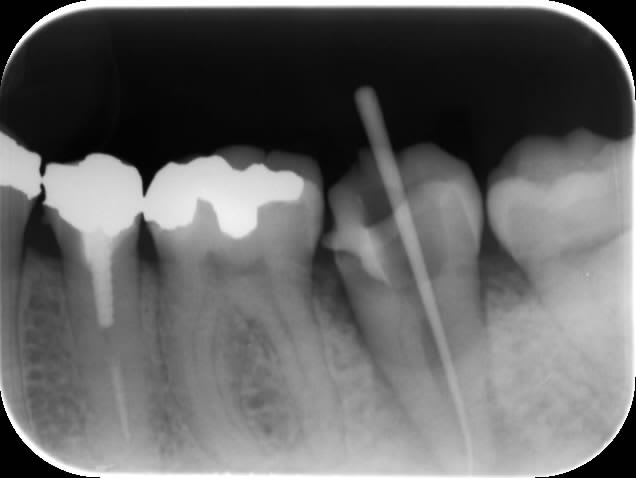

Endo 37 canal secondaire vers espace interradiculaire?

Bonjour

Essaie plusieurs incidences: perpendiculaire médial distal. C’est rapide et pratique quand tu ne peux pas faire de 3D